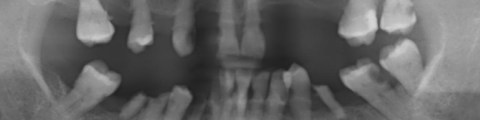

第三版的30年GBR,從261頁增加到340頁。章節也從九章增加到十四章,大致上,增加了前一版沒有的拔牙窩形變、立即植牙、前牙軟硬組織美學、植體周圍炎、補骨併發症。還有減少Bone Block的內容,字型也改成容易閱讀,不易疲勞的襯線體。

●第四章提到拔牙窩的改變,這也是這一版新增的章節。這邊簡單整理拔牙後,硬組織、軟組織的變化。篇幅不長,對年輕醫師,想簡單看一篇統整文章,可以從這裡開始。

●第五章,新增一整章節,整理影響補骨的因素,從植體選擇、植體種植位置、缺損區分類,許多前一版沒有的精美卡通圖,非常詳盡。光是水平骨缺損,就詳細分類了三大項,七小項,挺複雜的。其實說穿了,這邊分這麼多種,好像很難,其實背後的含義,就是將難度區份成不同等級,彼此使用的材料、手術技巧、介入時間與思考,是不一樣的。第六章的植牙時機,也是同樣在ITI Treatment Guide可以看到。